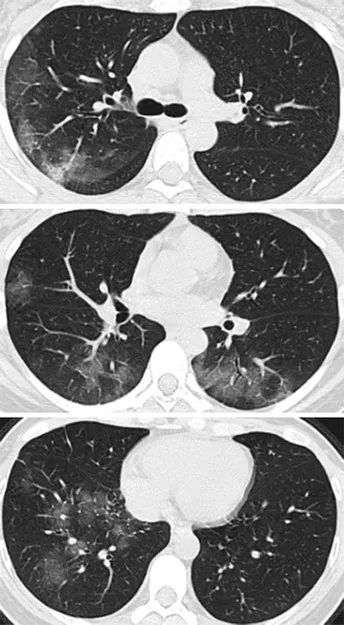

病例2,41岁女性,去了一趟武汉,

回来后,开始发热咳嗽,

4天后,她感觉呼吸困难,

去医院X线胸部拍片,检验血液,

都没有发现有啥异常。

但是CT扫描发现

两侧肺周边出现多处斑片状毛玻璃样显影。

图片来自《Radiology》杂志

来自Internet图片搜索

采用CT三维成像技术,

暴露在人们裸眼眼前,

到处是斑片状磨玻璃影(见下图)。

图片来自Radiology